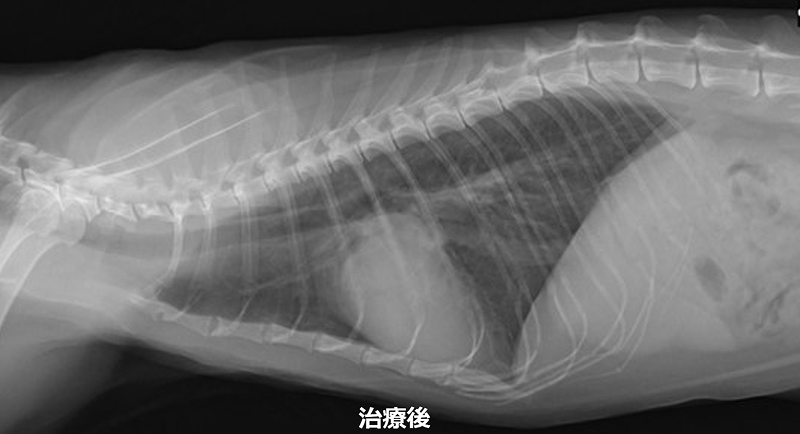

猫の心筋症 治療前と治療後

心筋症は心臓の壁が厚くなることで、心臓の中に十分に血液が入らなくなり、全身へ血液を上手く送り出せなくなります。早期の段階では、心臓が頑張って働くことにより全身に大き影響はありませんが、心臓が限界を迎えると心不全の状態となります。

病気がかなり進行するまでは、ほとんどの子で無症状です。心不全となり、肺水腫や胸水などにより呼吸が速くなったり、食欲が落ちたり、あまり動かずじっとしていることが多くなります。

また、心臓内で血液がうっ滞することにより、血栓が出来やすくなります。血栓は、肺や腎臓、足の血管に詰まります。腎臓につまると血尿が出たり尿が出なくなったります。足の血管につまると、足が急に動かなくなり激しく痛がることがあります。

心筋症の症例でも心臓に雑音が認められるとは限らないため、心臓の音が正常でも油断できません。そのため、中年齢になったら、定期的に心臓の検査を受けることをお勧めします。

心筋症は、手術で治すことは出来ないため、薬による内科治療で治すことになります。当院では、心臓超音波検査を行い治療薬を調整することで肺水腫や血栓症になるリスクを軽減することができます。

内科治療を行うことで、心筋症の進行をゆっくりにして心不全になるまでの時間を伸ばすことや、心不全の症状を和らげることが出来ます。また、心筋症の進行による血栓予防として抗血栓療法も行なっております。